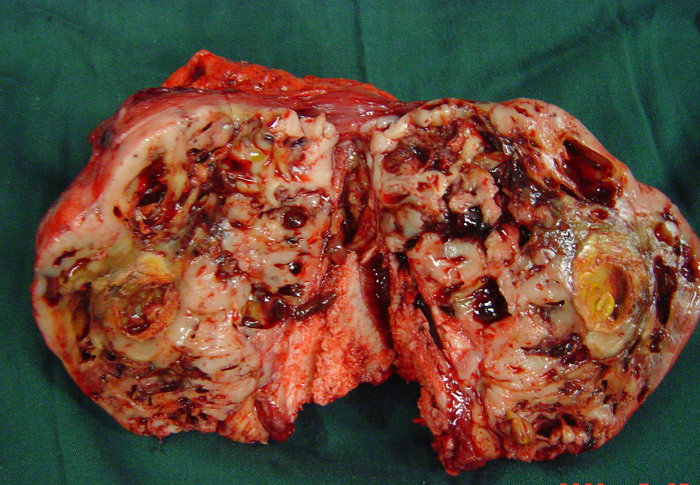

6、病例6:女 18岁 左半骨盆骨肉瘤,全身及肿瘤局部选择性动脉灌注大剂量化疗后行肿瘤切除人工半骨盆假体置换术

图 41 肿瘤标本

a:外观象 b:剖面象